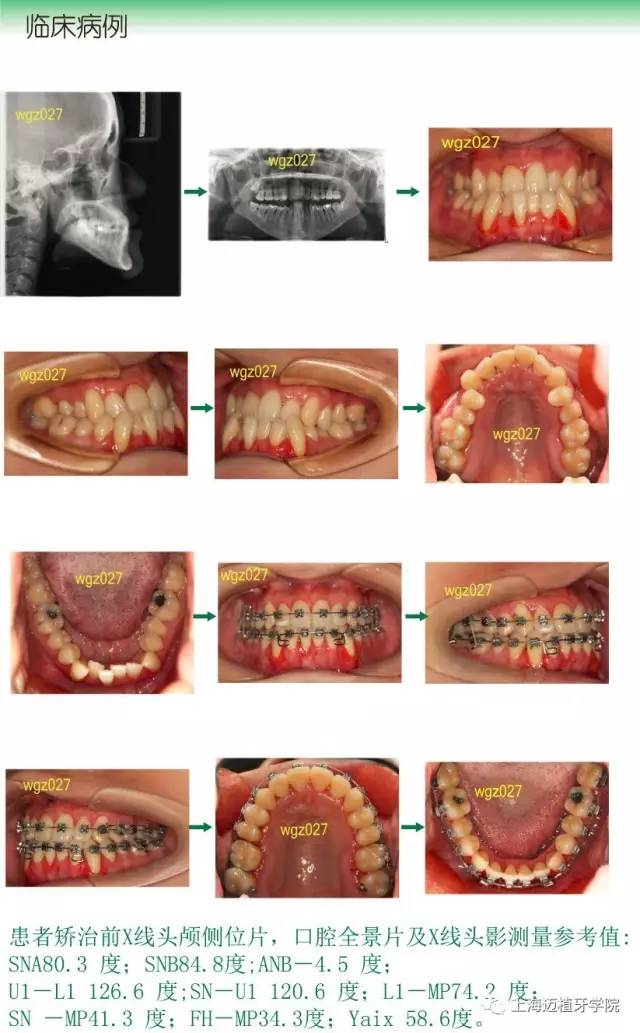

3、安氏III類錯合畸形的病例診斷分析及矯治流程